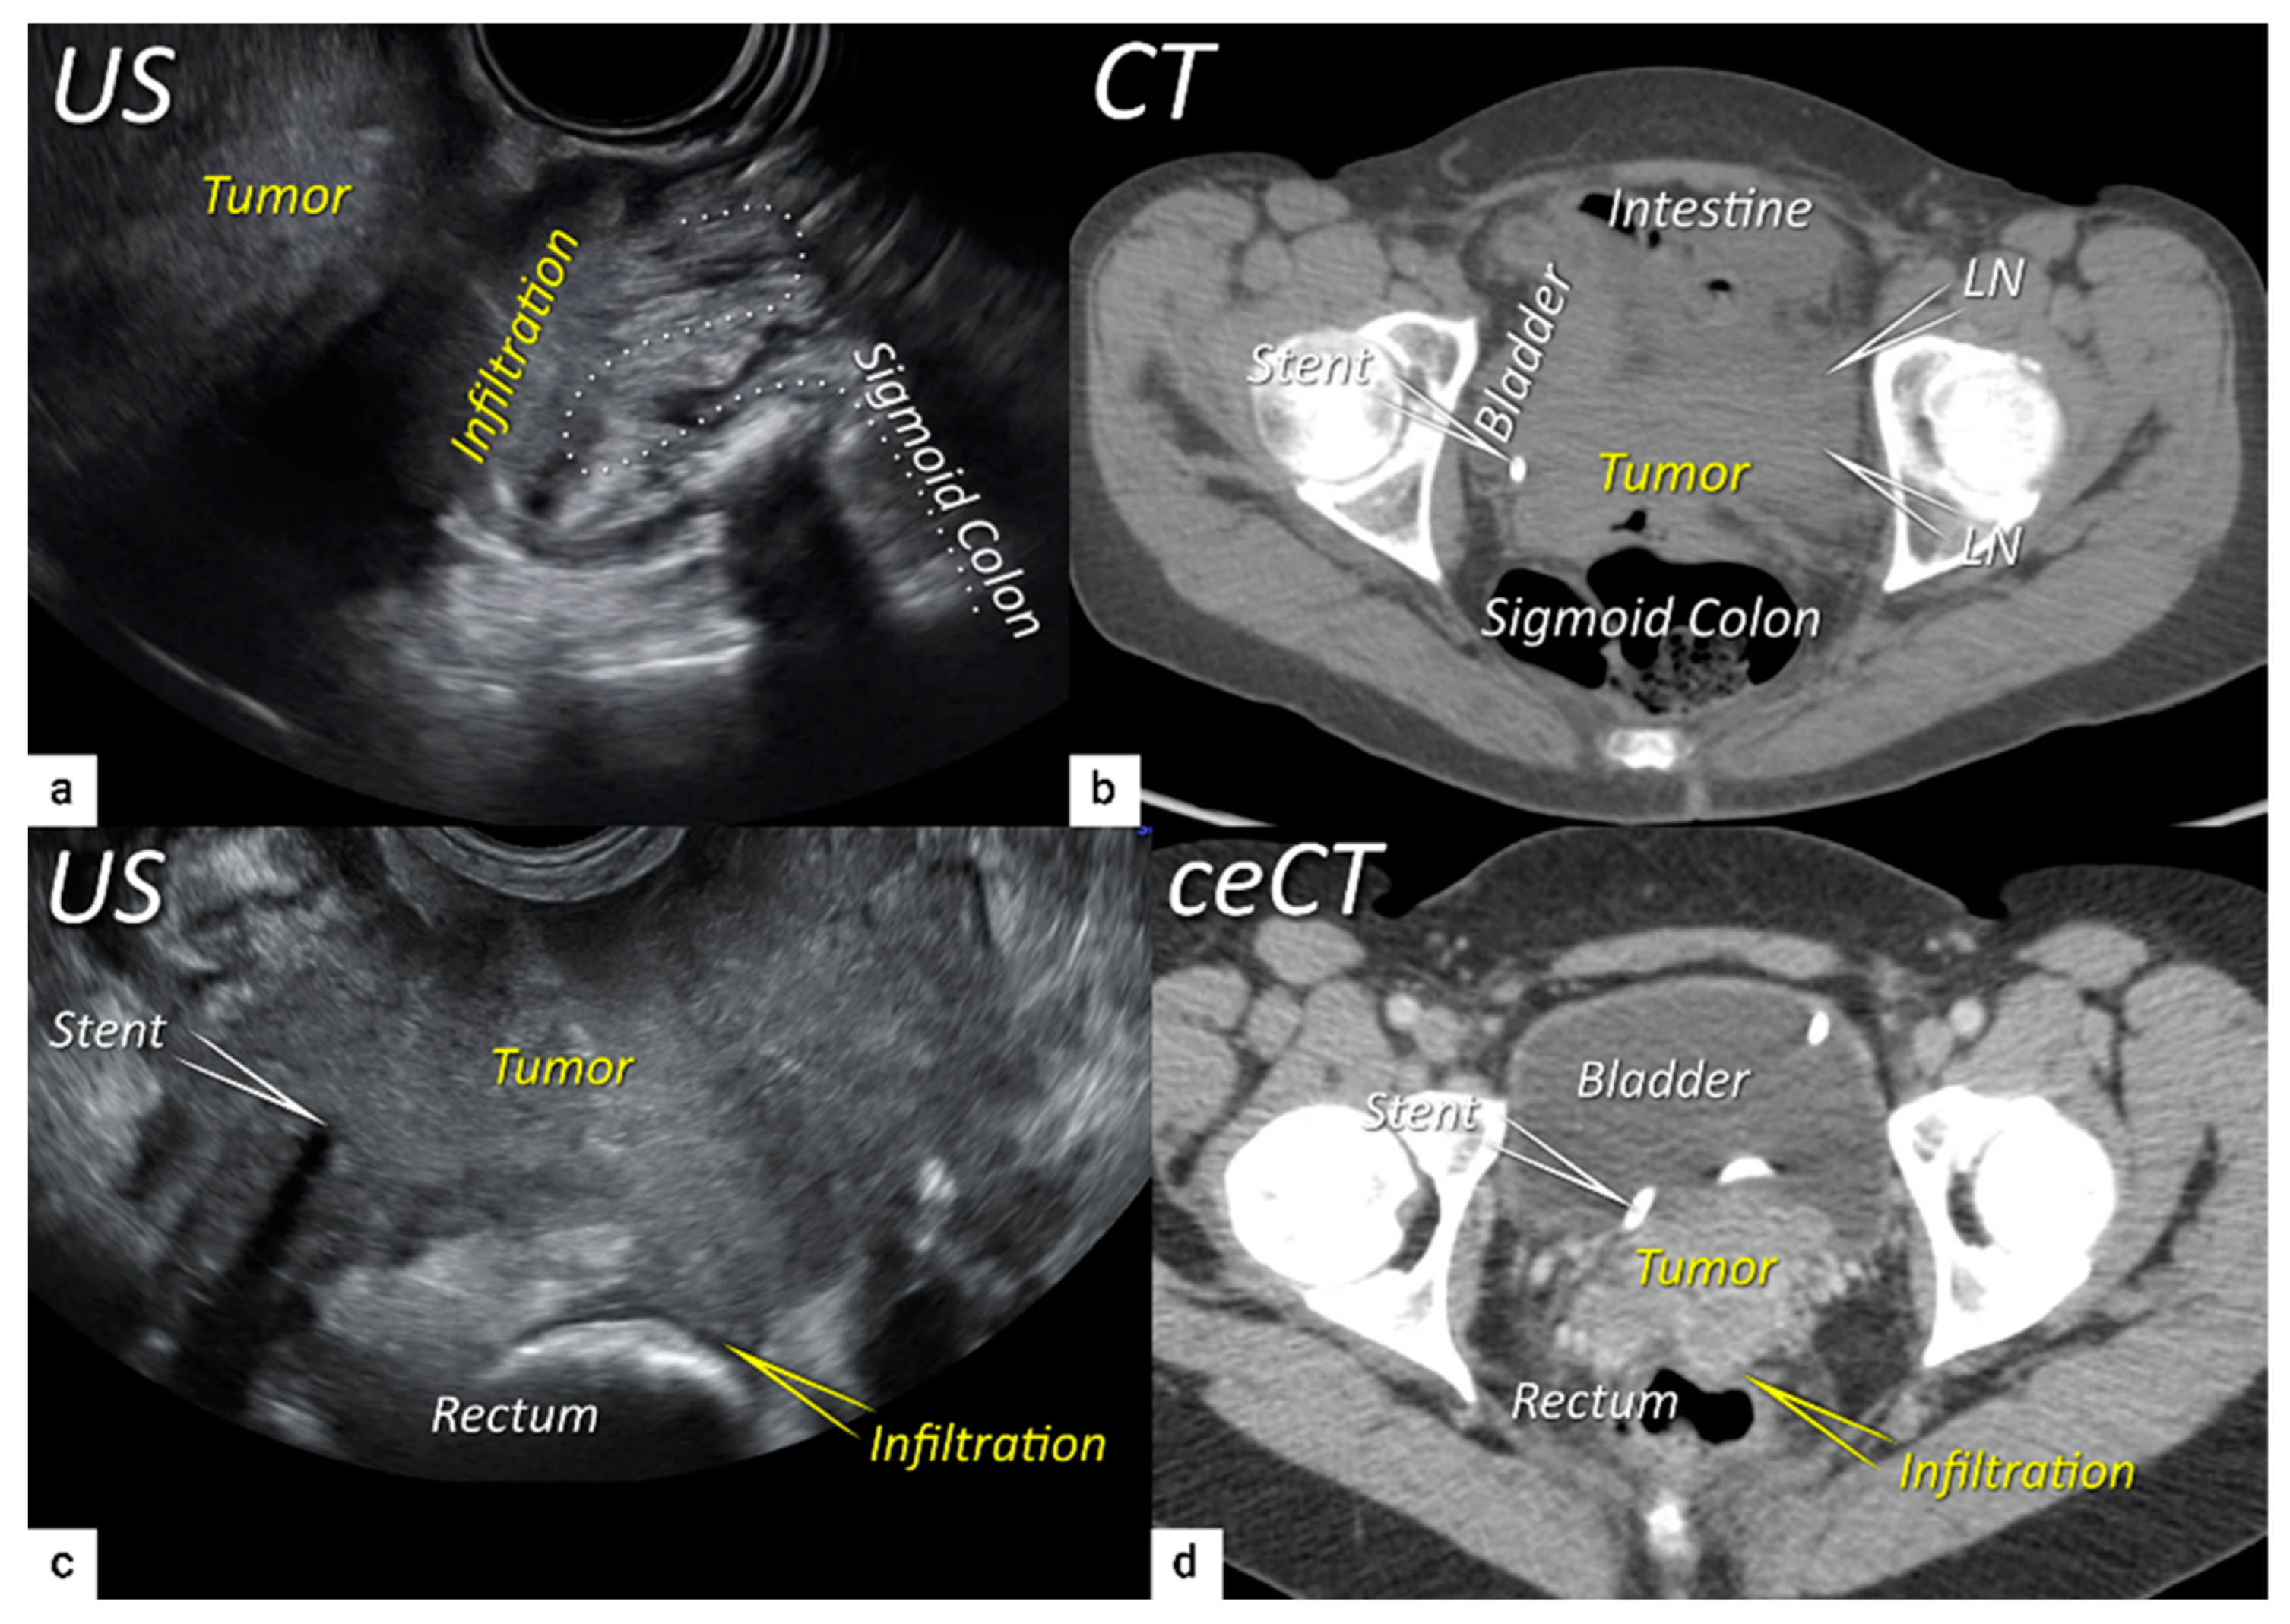

3.4. Extension to Surrounding Organs (Bladder, Rectum, Sigmoid Colon)

| T4 f | IVA f | Tumour invasion into the mucosa of the bladder or rectum (biopsy-proven) or into adjacent organs. | Tumour invasion into the mucosa of the bladder or rectum on imaging, confirmed by biopsy. US: Negative sliding sign, hypoechogenic tumour infiltration of bladder/rectal wall up to echogenic mucosa with polypoid tumour seen intraluminally. MRI: Focal or diffuse disruption of the normal T2-low signal intensity wall of the bladder/rectum, irregular or nodular wall, sometimes including an intraluminal tumour mass. Bulous edema sign, which is hyperintense thickening of the bladder mucosa on T2W images, is only an indirect sign of invasion and should not be regarded as T4 unless confirmed mucosal infiltration at cystoscopy. Infiltration of the posterior bladder wall without mucosal infiltration should not be regarded as T4a. |